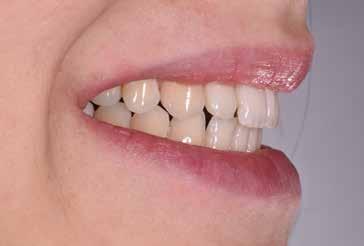

97 96 ESTETICA FUNZIONE POSTURA 145 _ Profilo sinistro con sorriso. 146 _ Ripresa di 3/4 sinistra con sorriso. 147 _ Immagine frontale naturale, senza sorriso. 148 _ Immagine frontale con sorriso. 149 _ Ripresa di 3/4 destra con sorriso. 150 _ Profilo destro (senza) con sorriso. 151 _ Dettaglio del sorriso. 152 _ Dettaglio del sorriso nel profilo destro. 153 _ Dettaglio del sorriso nel profilo sinistro.